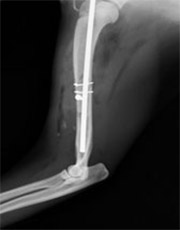

前肢上腕骨骨折

このタイプの骨折は猫、特に外に行く猫ちゃんに多く、高い所から飛び降りて着地に失敗することで骨折することが多いです。

手術前

手術後

この箇所の骨折は筋肉が多く、強度の高い固定が必要です。また今回みたいな斜骨折が多く認められます。髄内ピン、スクリュー、ワイヤーで治療を行いました。